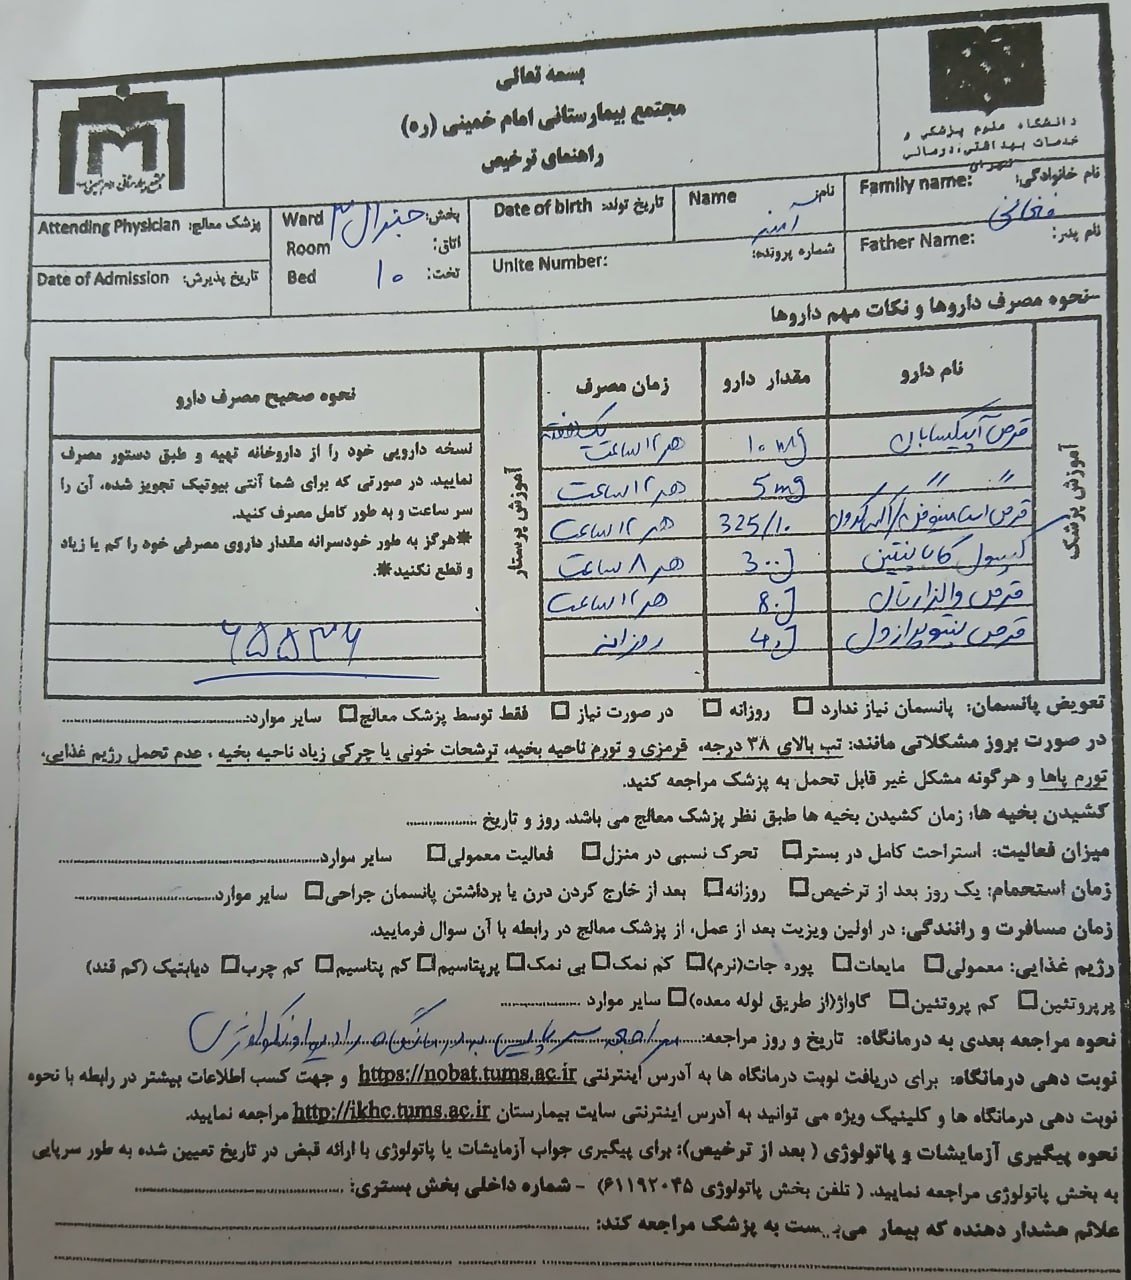

Pentomid 40

Valsartan 80

Apixaban 5

Caltonix 200 I.U.

gabapentin 300

(تصویر مربوط به این مراجعه نیست) Other:

(تصویر مربوط به این مراجعه نیست) Other:

(تصویر مربوط به این مراجعه نیست) Other:

(تصویر مربوط به این مراجعه نیست) Other:

(تصویر مربوط به این مراجعه نیست) Other:

(تصویر مربوط به این مراجعه نیست) Other:

(تصویر مربوط به این مراجعه نیست) Other:

(تصویر مربوط به این مراجعه نیست) Other:

(تصویر مربوط به این مراجعه نیست) Other:

(تصویر مربوط به این مراجعه نیست) Other:

(تصویر مربوط به این مراجعه نیست) Other:

(تصویر مربوط به این مراجعه نیست) Other:

(تصویر مربوط به این مراجعه نیست) Other:

(تصویر مربوط به این مراجعه نیست) Other:

(تصویر مربوط به این مراجعه نیست) Other:

(تصویر مربوط به این مراجعه نیست) Other:

(تصویر مربوط به این مراجعه نیست) Other:

(تصویر مربوط به این مراجعه نیست) Other: